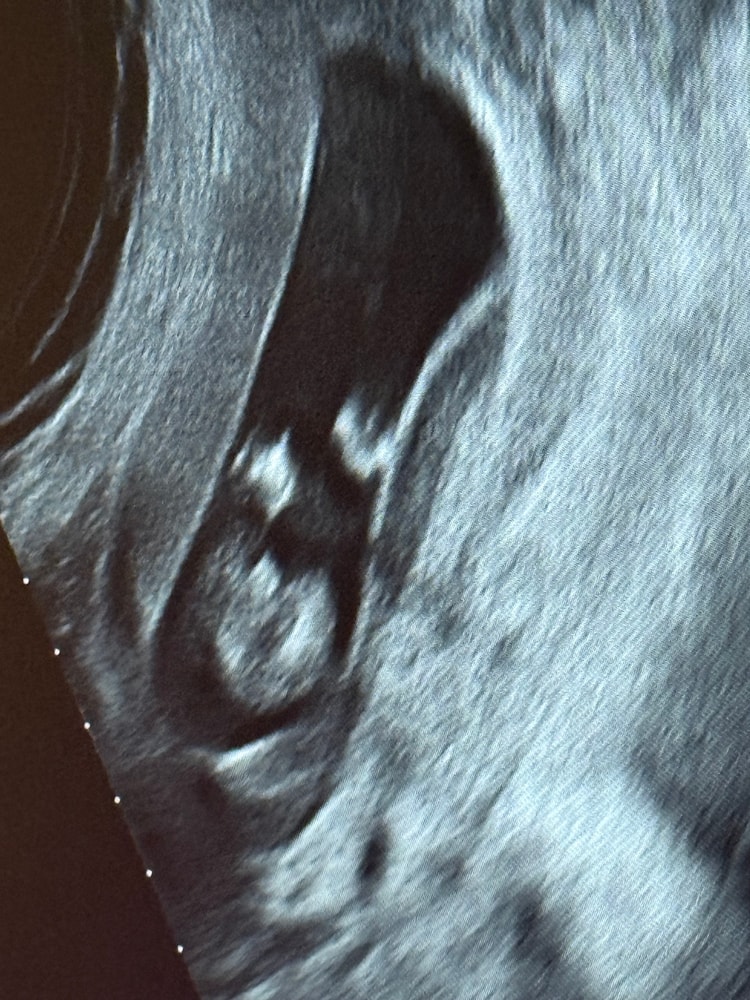

Похоже ли на член?😅 Пол малыша по узи